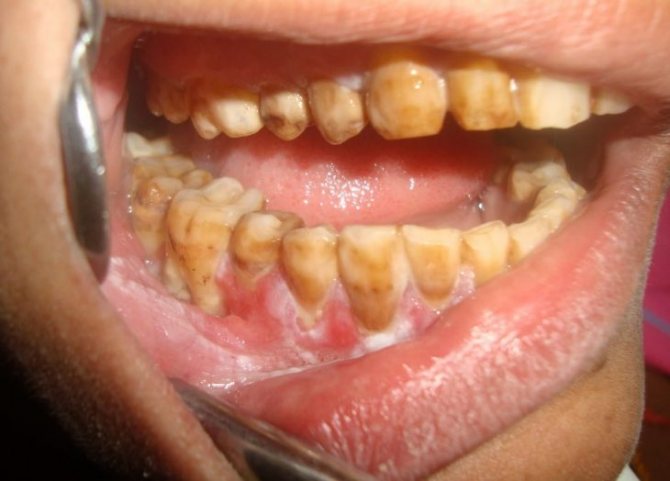

Фото лейкоплакии

Участок поврежденных поверхностей выглядит как гиперкератозная пятнистость – нестандартного разрастания внешних слоев, визуально определяющиеся как измененный эпителий мутного цвета, с четким разграничением.

Уровень повреждения тканей может быть разной интенсивности, на его фоне цветовая окраска пятен от сероватого до молочно-белого оттенка. Участки, затронутые аномальным процессом, шероховатые и сухие. При пальпаторном исследовании уплотнения не обнаруживаются, внешних признаков воспаления не существует.

Симптоматическим проявлением болезни служит разрастающееся ороговение, вызывающее значительное увеличение и утолщение верхних слоев слизистых покровов. Участки веррукозного поражения находятся выше рядом расположенных тканей, отличаются резким цветовым оттенком. Пальпаторное исследование подтверждает наличие поверхностного уплотнения.